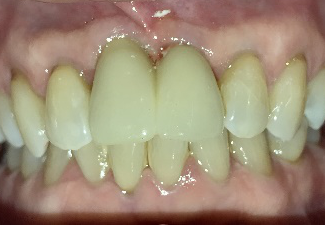

女性Tさん 60代(インプラント)

上の前歯の部分入れ歯が合わないので、インプラントにしたい。

治療内容

インプラントを4本埋入しました。

所感

骨の厚みが薄かったのですが、X-Guideを用い、正確に埋入することが来ました。

治療後「とてもきれいに出来てうれしかったです。話をしても、空気がもれず良くなりました。もう少し早く治すと良かったと思いました。」と、とても喜んでくださいました。

Before

インプラント埋入前

義歯を装着したところ

使用していた部分入れ歯

After

インプラント埋入後